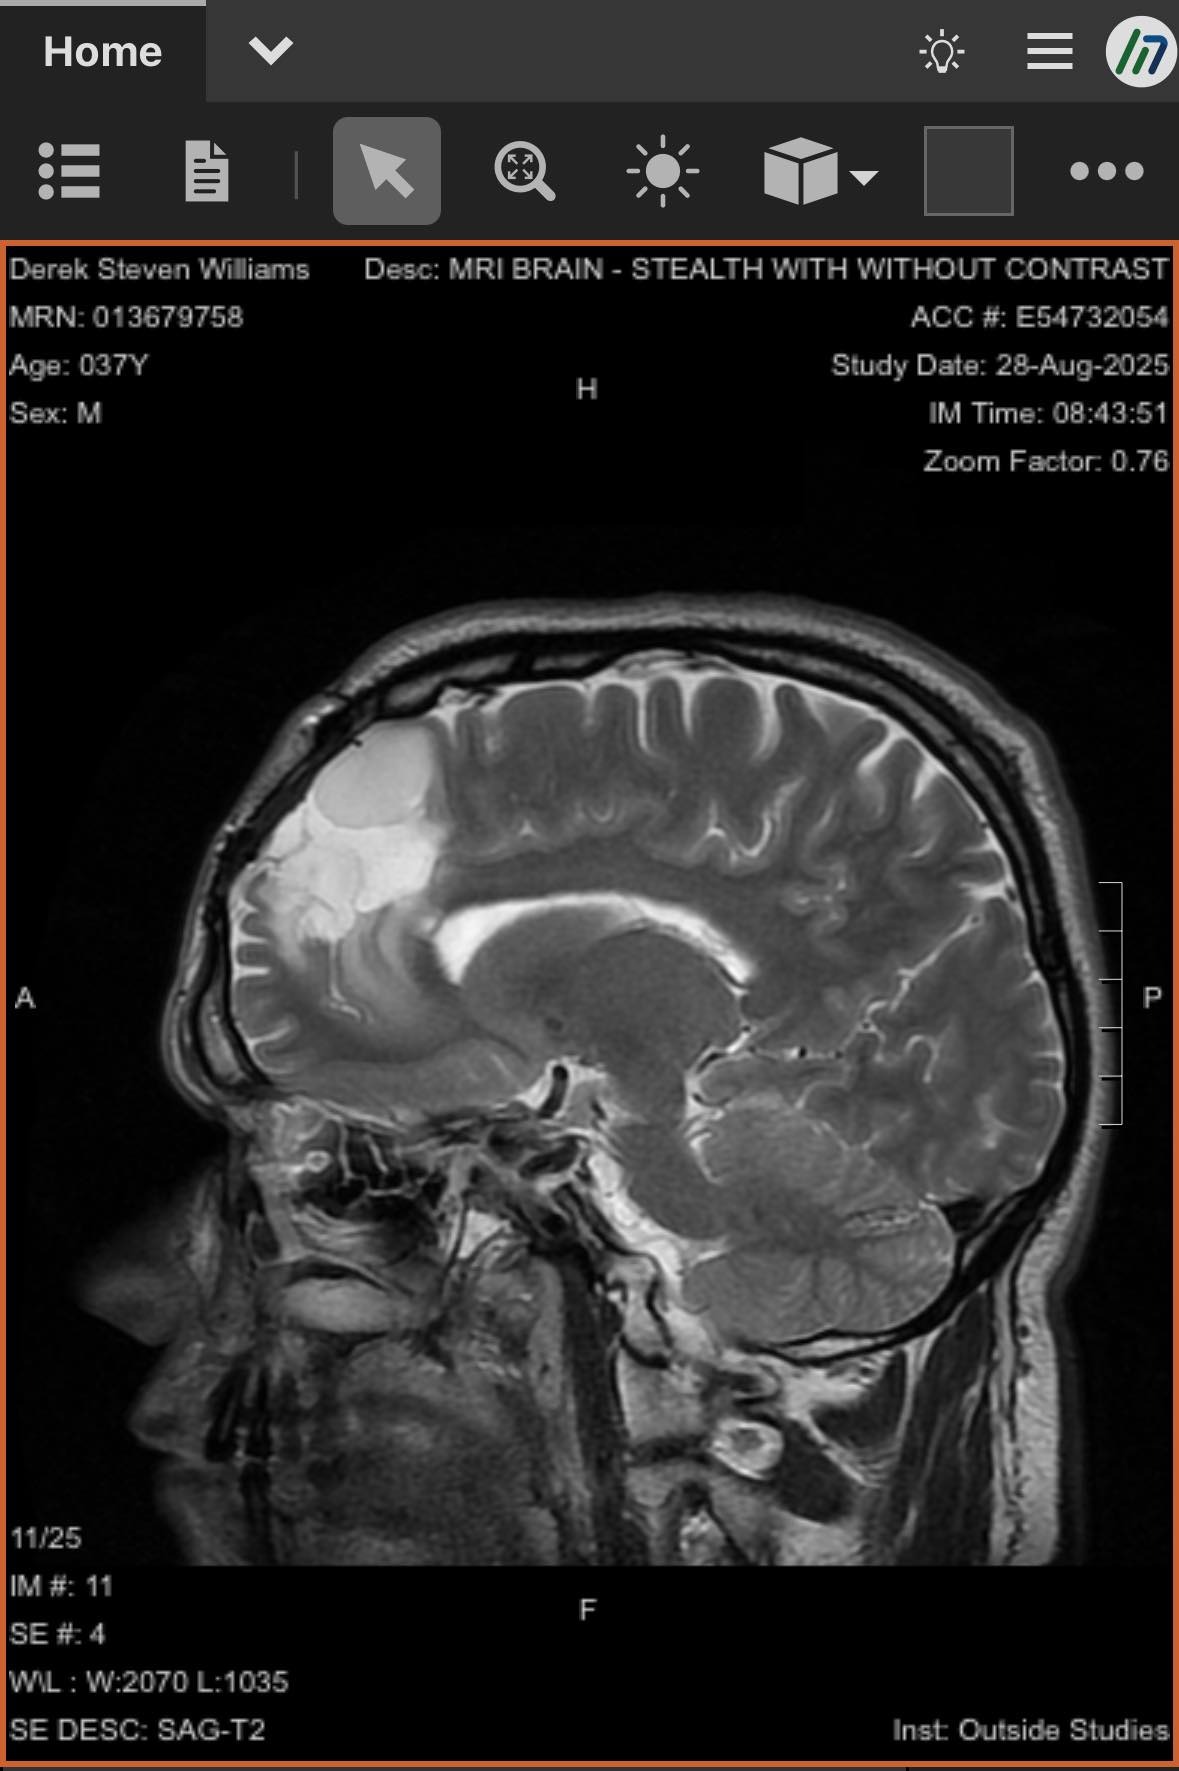

-Derek currently has two potentially deadly infections in his spinal cord, along with IDH Mutant or Astrocytoma, which is a brain cancer that there is currently no cure for. On top of all of this, he has developed 3 masses on and in his liver. With his current regimen of over 20 pills a day, driving to Lexington for appointments 6-8x a week and to Vanderbilt often, as well being a Dad and continuing his duties there, the financial burden has been significant. He has been fighting disability which feels like a losing battle for 2 years. -

Derek has been facing an ongoing battle with brain cancer and other medical issues. Most recently, he learned that he has a severe infection on his spinal cord, a cancerous tumor in his brain, as well as his liver. He has had to have a PICC line put in, and will be down for at least 8-10 weeks, if not longer. Insurance is being a pain and not wanting to cover many parts of his treatment, including home health, which is causing him to have to stay in the hospital, and miss valuable time with his son and best friend, Jayden.